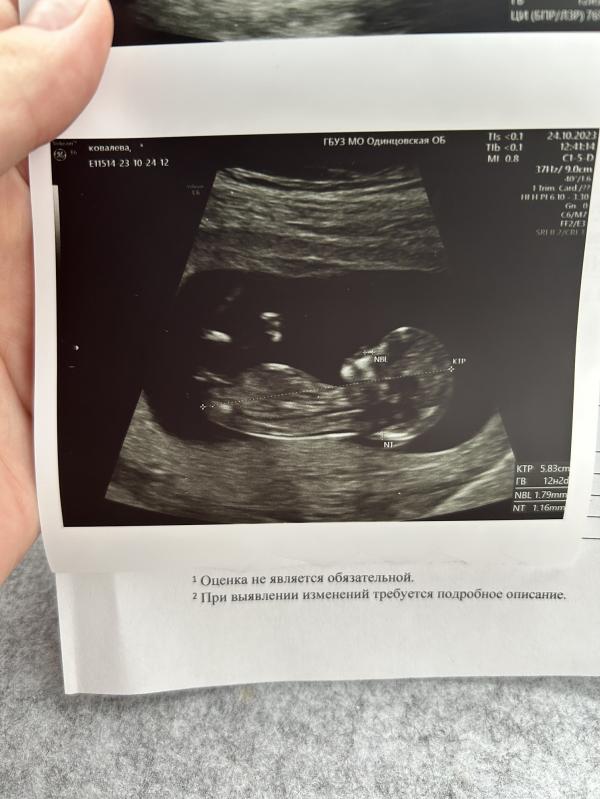

Первый скрининг при первой беременности: что увидела, эмоции и впечатления? Делюсь опытом!

Сегодня была на первом скрининге.. это такой волнительный момент. Я впервые увидела своего малыша на экране😍

Беременность первая, очень долгожданная🙏🏻